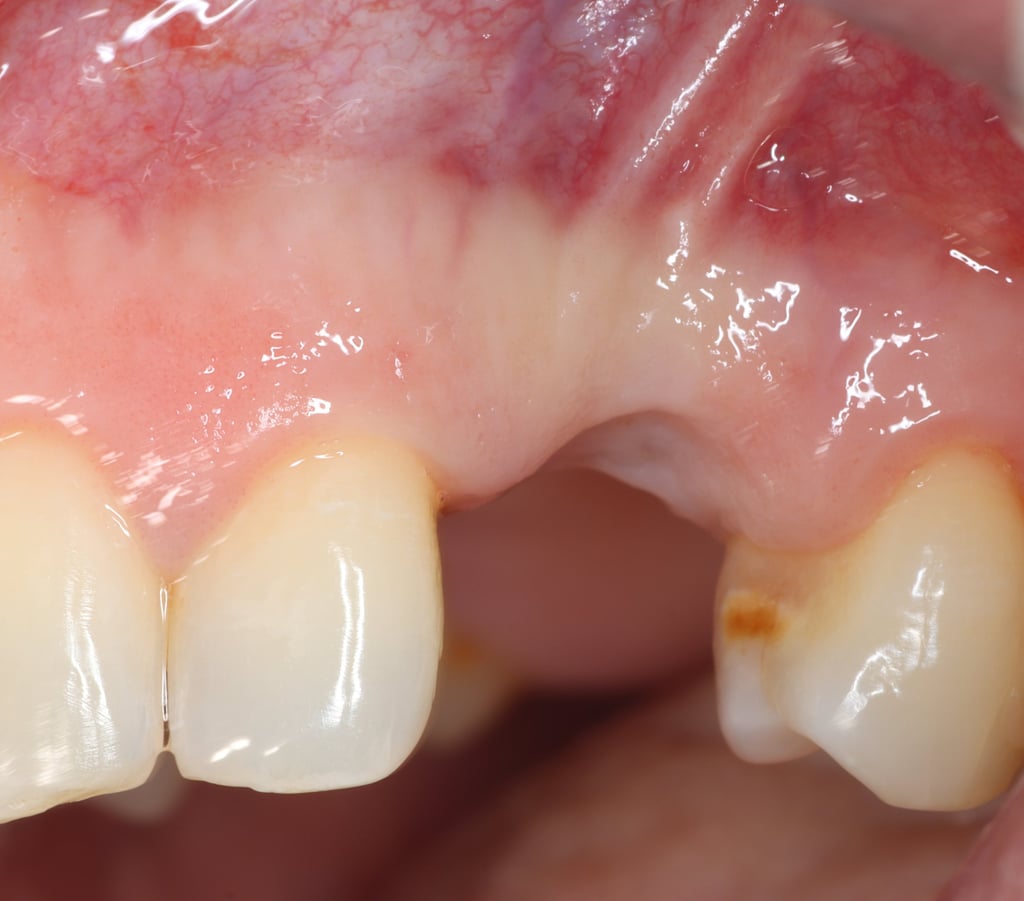

Chirurgie muco-gingivale

Traitement des récessions gingivales